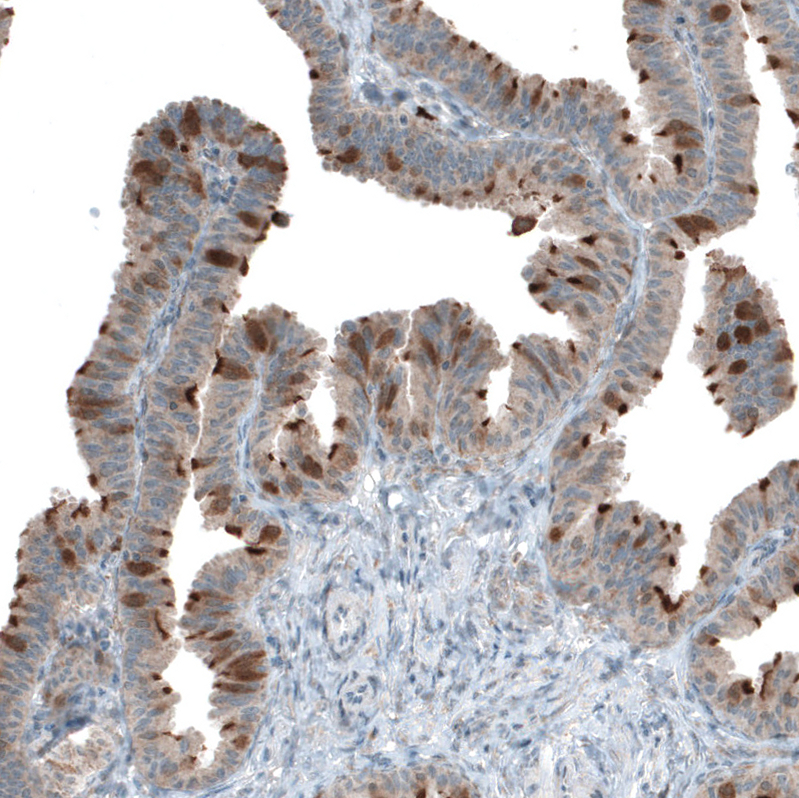

Immunohistochemistry analysis in human fallopian tube and skeletal muscle tissues using HPA027379 antibody. Corresponding CDK20 RNA-seq data are presented for the same tissues.